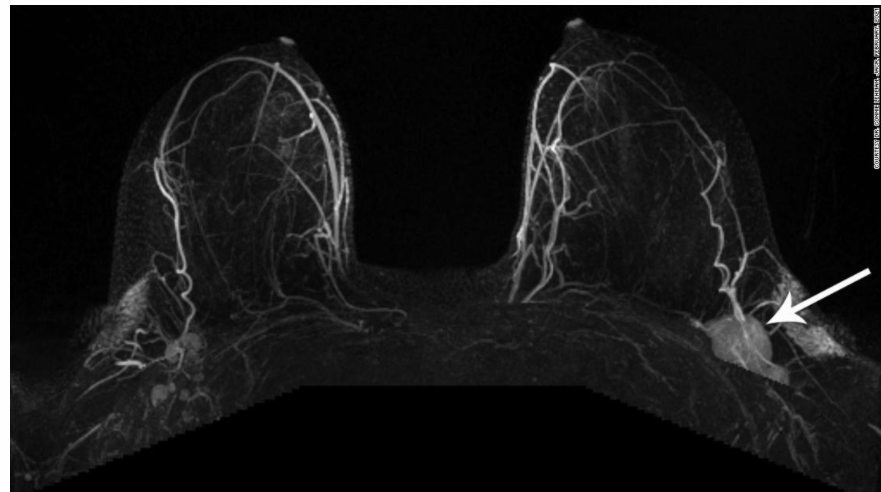

Devon Quasha是一名医护人员,平时就很关注自己的身体健康,所以当她发现乳房周围有肿块时,便立即预约了X光和超声检查。

在做检查的前几天,Devon感觉整个左臂、腋下和锁骨上方的部位都开始出现异常的肿胀。

万幸的是,医生看了报告认为她患癌症的几率不大,并且告诉Devon,之所以出现肿胀的症状是因为她才接种过新冠疫苗。

原来在预约检查前的一周,作为医护人员的Devon注射了第一针Moderna疫苗。

相关数据显示,大约有10%的群众在接种第一剂Moderna疫苗后,腋下或锁骨周围的淋巴结部位会出现肿块,这也是打完疫苗后产生的常见副作用之一。

来自渥太华的乳房影像科主管医师Jean Seely表示,不仅是女性,男性在注射完疫苗后也会经历类似的副作用,通常在打完疫苗后数周内"发作"。

然而这个说法并不能让Devon感到完全放心,她的放射科医生也称,因新冠疫苗造成的肿块是一方面,可乳房周围出现的肿块是另一回事,需尽快进行活检确认。

但由于Devon打了疫苗没多久,医生又不建议她立刻进行活检检查,否则很可能导致被误诊为罹患乳腺癌。